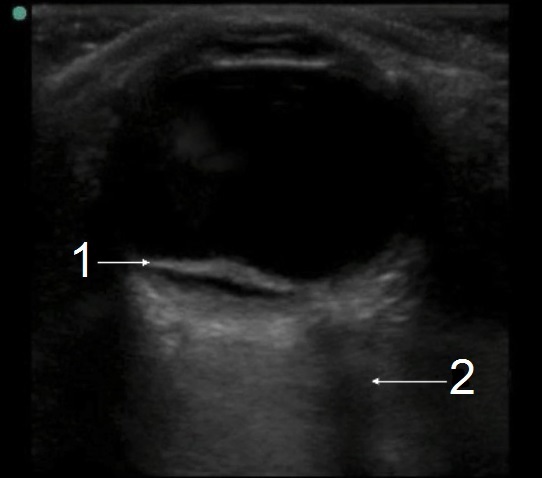

眼部视网膜脱离 – 锚定视神经图像

视网膜脱离 (RD)

视神经